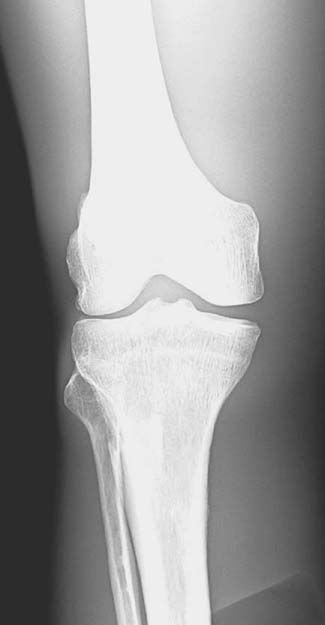

A radiographic image must have sufficient brightness to visualize the anatomic structures of interest (Fig. 3-13). A radiographic image that is too light has too much brightness to visualize the structures of the anatomic part (Fig. 3-14). Conversely, a radiographic image that is too dark has insufficient brightness, and the anatomic part cannot be well visualized (Fig. 3-15).The radiographer must evaluate the overall brightness in the image to determine whether it is sufficient to visualize the anatomic area of interest. He or she then decides whether the radiographic image is diagnostic or unacceptable.

FIG. 3-13 Brightness. Radiographic image with sufficient brightness. (From Johnston JN, Fauber TL: Essentials of Radiographic Physics and Imaging, ed 3, St. Louis, 2020, Mosby.)

FIG. 3-14 Brightness. Radiographic image with excessive brightness. Brightness altered with postprocessing. (From Johnston JN, Fauber TL: Essentials of Radiographic Physics and Imaging, ed 3, St. Louis, 2020, Mosby.)

FIG. 3-15 Brightness. Radiographic image with insufficient brightness. Brightness altered with postprocessing. (From Johnston JN, Fauber TL: Essentials of Radiographic Physics and Imaging, ed 3, St. Louis, 2020, Mosby.)